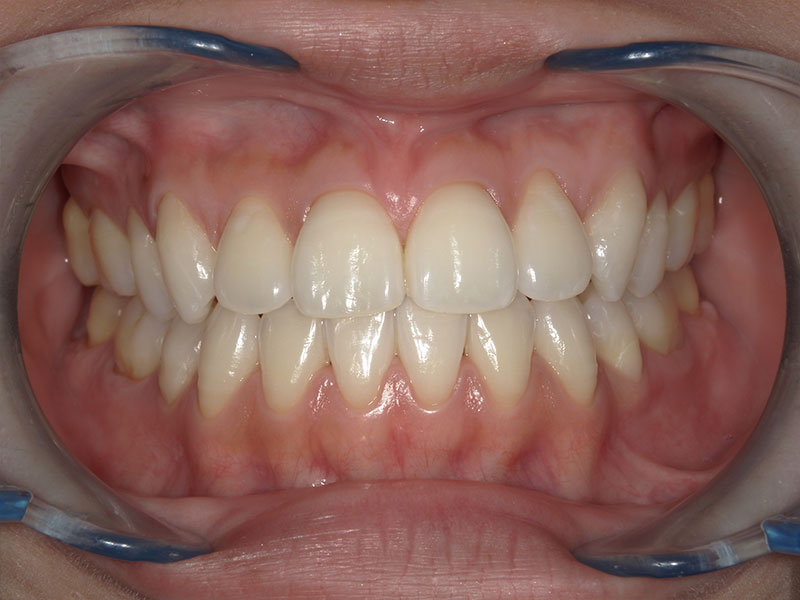

治療後

After

年齢 43歳

性別 女性

主訴 左下の乳歯を抜きたい